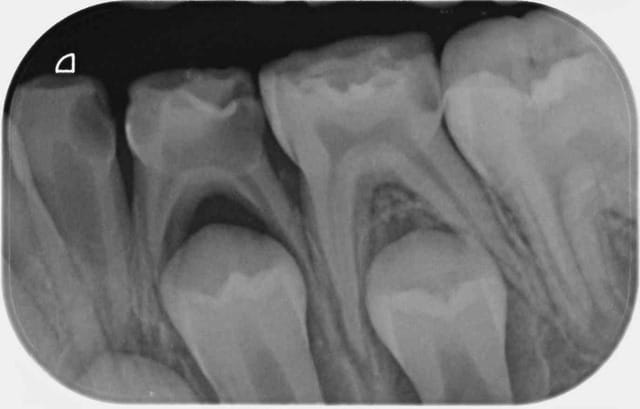

Possibilité d'avoir différentes tailles de capteurs : pour les dents antérieures voir pour des grandes rétro coronaires permettant d'avoir les DDS.

Qualité des images